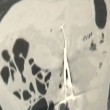

Dopo essersi rassegnato a provare dolore perennemente, Karp da un mese aveva cominciato a dimagrire perdendo anche l’appetito. Ha così pensato di recarsi all’ospedale per una visita e lì, grazie ai raggi x, hanno scoperto l’arcano.

Le forbici che aveva nello stomaco era quelle utilizzato da chirurghi e lunghe quasi 20 centimetri. I medici hanno raccontato di non aver mai visto niente del genere.